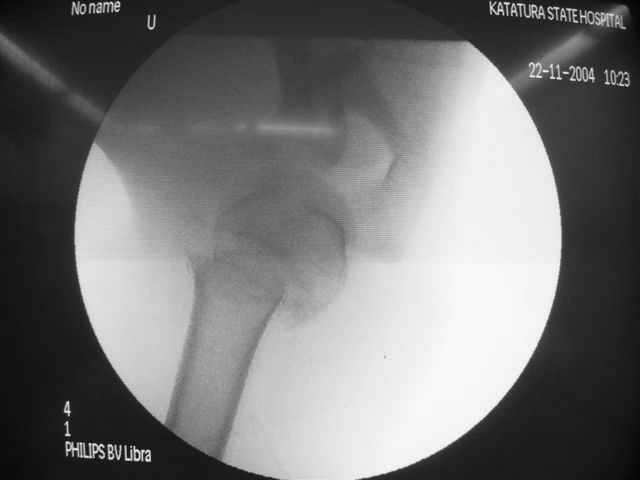

Коллеги, Больной прооперирован вчера. 19 летний пациент с переломом шейки плеча. Закрытая репозиция и чрескожная фиксация спицами под контролем ЭОПа ( техника проф. Лазарева)

Интраоперационный контроль на стабильность фиксации - сомнений в стабильности фиксации не возникло. Послеоперационный контроль сегодня......